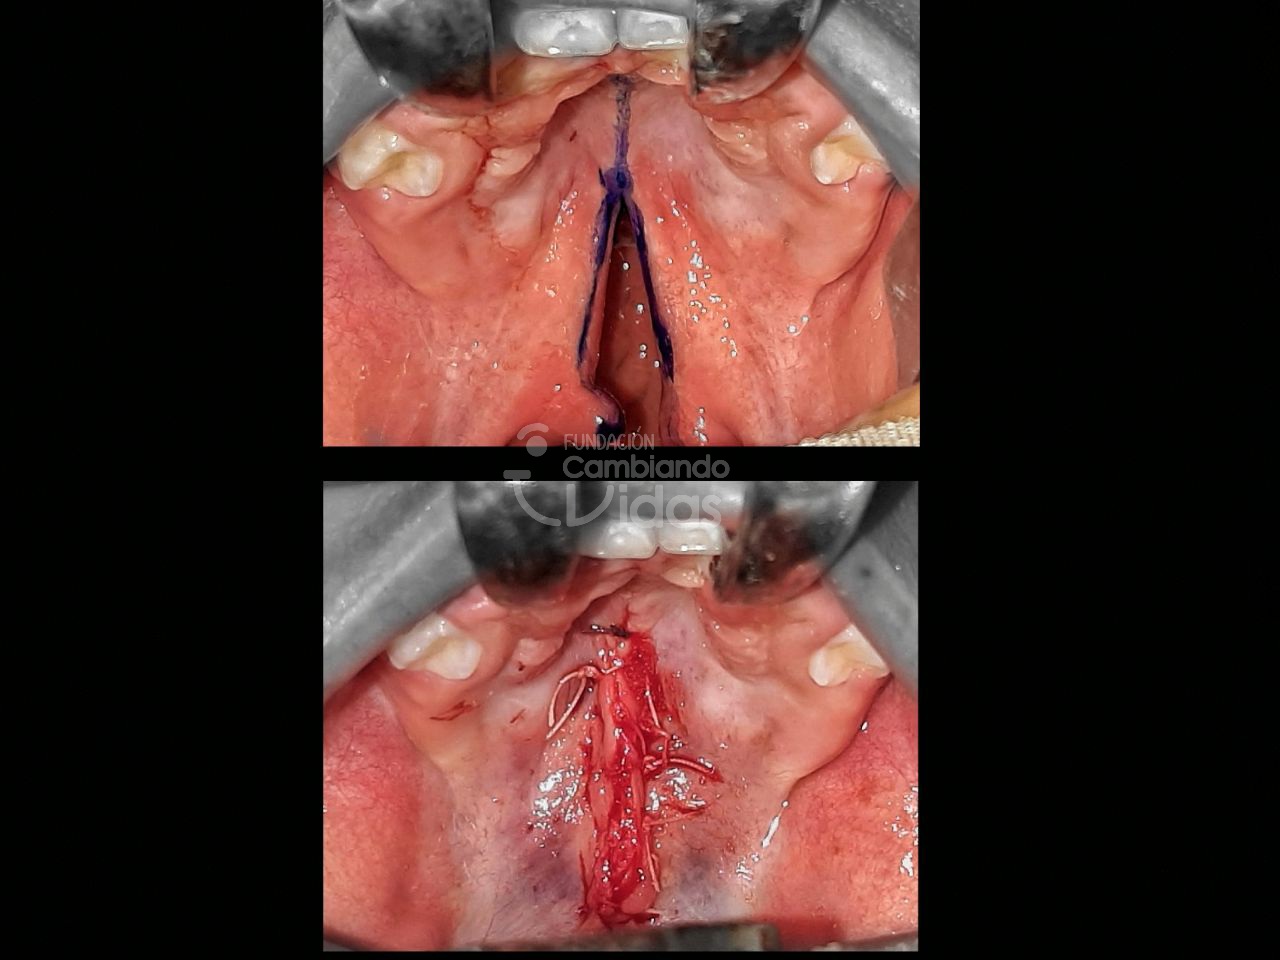

Leiner Guerrero

Diagnóstico: Lactante Mayor de 2 años con Hendidura Palatina Completa

Intervención Quirurgica: Palatoplastia Primaria